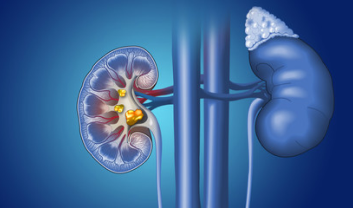

Kidney stones are solid deposits that form in the kidneys when substances like calcium, oxalate, and phosphorus become concentrated.

PUJO obstruction occurs when there is a blockage at the point where the kidney's pelvis connects to the ureter, hindering the natural passage of urine..